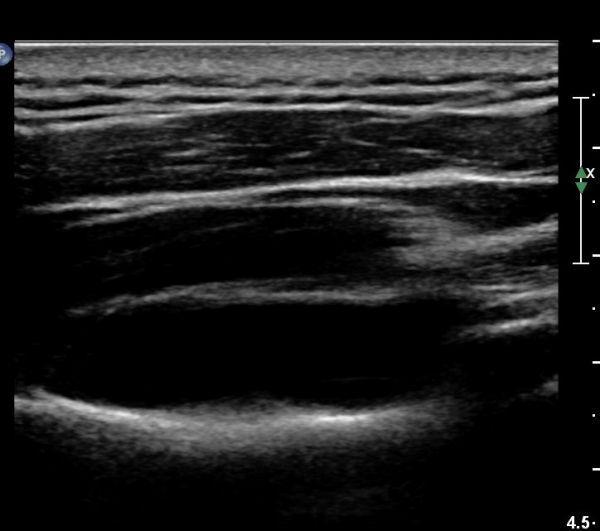

¾î±ú µÚÂÊ È¾´Ü¸é°Ë»ç¿¡¼­ °üÀý¿Í(glenoid) ³»Ãø¿¡¼­ ¸¹Àº ¾çÀÇ ¼ö¾×Àú·ù°¡ °üÂûµÈ´Ù(»çÁø 1, 2).

ÄÁº¤½ºÅ½ÃËÀÚ¸¦ ÀÌ¿ëÇÑ ¾î±ú µÚÂÊ È¾´Ü¸é°Ë»ç¿¡¼­ °üÀý¿Í ³»Ãø ¼ö¾× Àú·ù¿Í °üÀý¿Í¼ø ÆÄ¿­ÀÌ

°üÂûµÈ´Ù(»çÁø 3, 4, 5, 6).